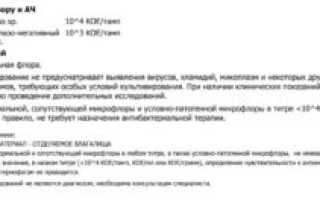

Коагулазонегативные стафилококки: что это, особенности и лечение В природе существуют микроорганизмы, способные вырабатывать токсины, нарушающие жизнедеятельность клеток живого организма, разрушительно...